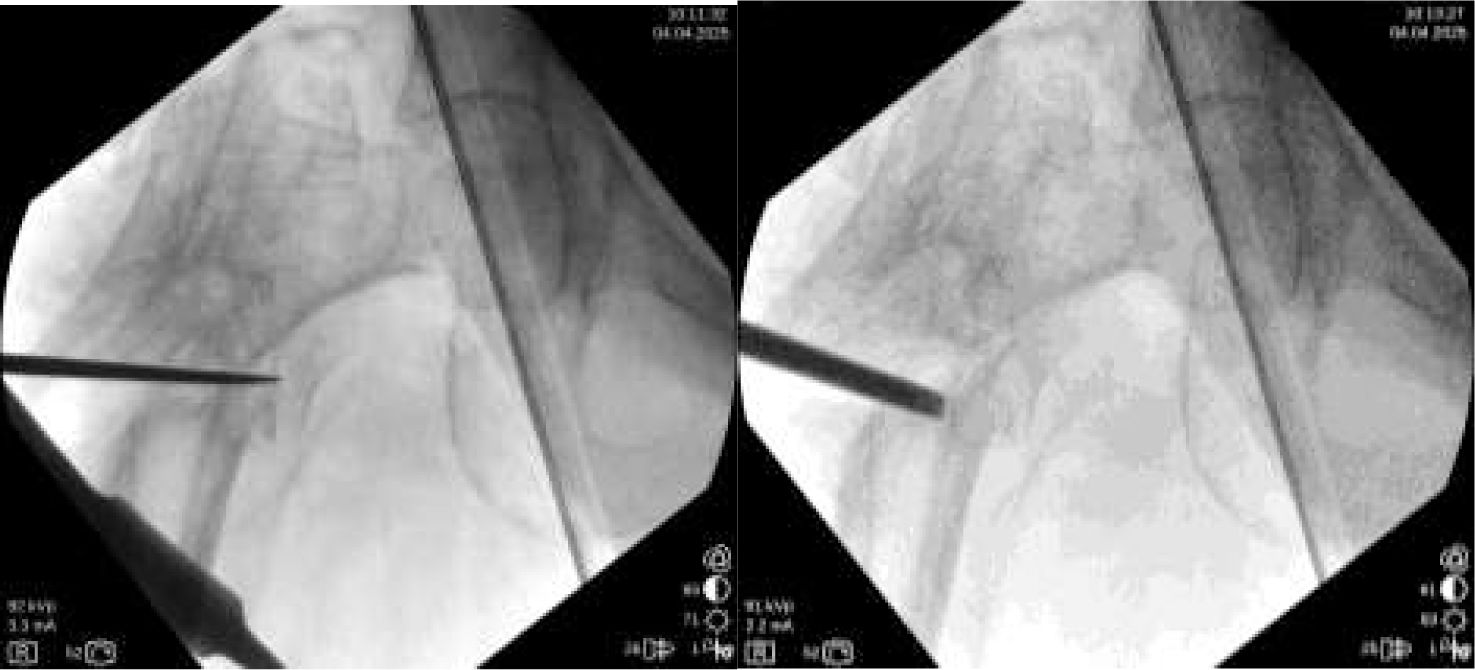

The goal of the surgical technique is to overcorrect the varus deformity to get a final 150° valgus angle at the femoral neck. It is also important that the distal part of the proximal side of the nonunion be in contact with the distal part (diaphyseal bone), to get a dynamic compression from the first postoperative day (Fig. 1).

A radiographically calibrated image of the proximal femur of the patient should be used. An AP Pelvis X-ray should be taken with both knees in 15° of internal rotation. Over this template, measurements are done.

It is recommended to use a 150° plate for “low” nonunions, and a 135° plate for “high” nonunions (more proximal nonunions). If we use the 150° plate, the cephalic screw should follow the central axis of the femoral neck. Nevertheless, If we use the 135° plate, to get 150° of valgus at the neck, the path for the cephalic screw must be 15° of varus (Fig. 2). The tip of the screw should be as near to the center of the hip as possible. Anyway, a slight downward position of the tip of the screw is possible (as seen in Fig. 1), if necessary, to avoid the same hole as the previous implant.

Lines are drawn as seen in Fig. 2. It is useful to measure the distance of the entry point to de tip of the greater trochanter, or the hole of the previous implant, or any other reference to be seen later on fluoroscopy. That will be the final position in AP view. In the lateral view, the screw should be just in the center.